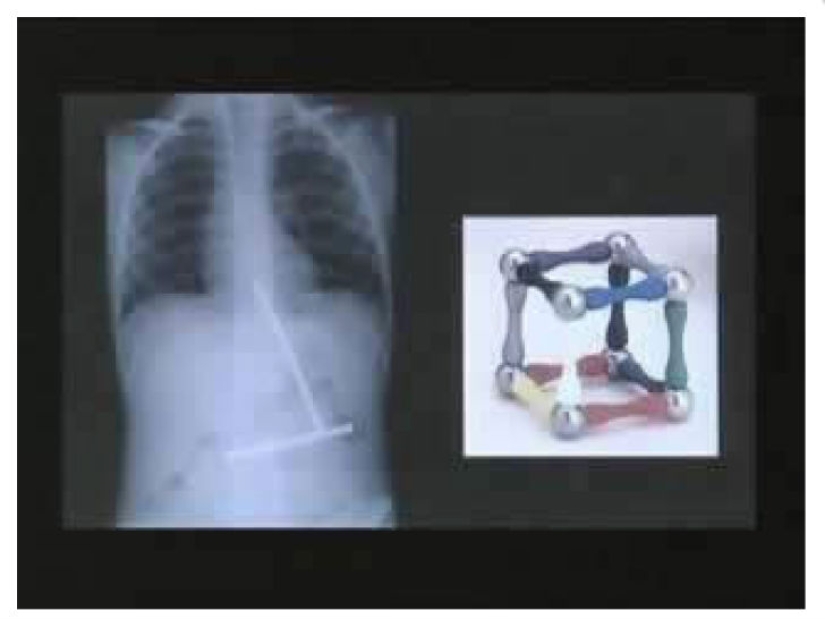

One little boy ate one part of a toy with a magnet at a time. When at last all the parts of the toy were in the boy's stomach, they connected.